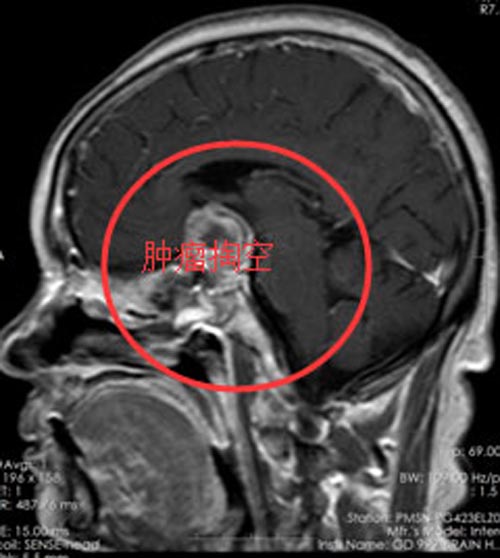

入住广东三九脑科医院垂体瘤诊疗中心,头颅MR提示:鞍区示团块状稍低、高混杂信号影,范围约3.7cm×2.6cm×2.4cm,垂体炳及视交叉显示不清,邻近双侧颈内动脉受压,左侧部分被包绕。

诊断明确后,李阿姨及家属要求手术治疗。由鲁明副院长主刀经鼻蝶行垂体瘤切除术,手术顺利。术后,李阿姨非常开心:不但左眼视力明显改善,看东西清晰了,而且没有开颅,满足了保留头发的心愿。